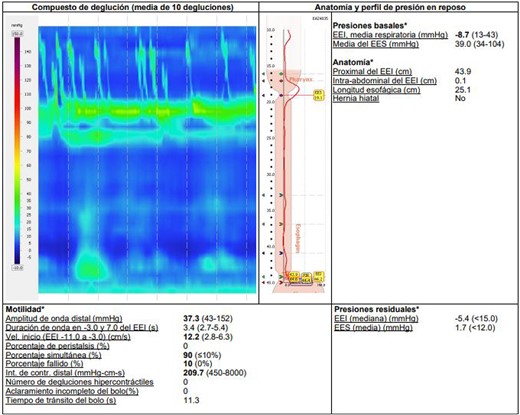

Additional diagnostic procedures included videoendoscopy, which revealed grade II megaesophagus and gastroscope-adjusted hiatus to the retroversion maneuver with signs of competent fundoplication. Esophagogastroduodenal transit with barium contrast (Fig. 1) showed adequate passage from the esophagus to the stomach with fundoplication on diaphragmatic arches, suggesting the presence of a hiatal hernia with intrathoracic stomach contents. Return of contrast after swallowing suggests reflux, presence of tertiary waves, stenotic area in cardia, and megaesophagus without alteration of gastric emptying. The patient showed normal phmetry and manometry (Fig. 2) with difficulty in passing the probe through the lower sphincter, presumably due to hypertension or lack of relaxation and esophageal body activity with panpressurization, classified as achalasia evolving from type I to type II.

Esophageal manometry with evidence of panpressurization (achalasia type II).